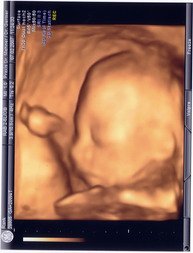

ich versuch mal das 3d bild meiner püppi reinzusetzten, mal schauen ob ich s hinbekomme:

Anhänge

• 3d kleiner.jpg

3d kleiner.jpg

14,6 KB · Aufrufe: 56

meine ganze verwandtschaft behauptet es würde aussehen wie mein großer sohn!!!!

ich freu mich auch sehr mein baby zu sehen. heute nacht habe ich wieder davon geträumt ind weil ich gestern abend noch gelesen habe, dass wulffine in 9 min ihr baby hatte hab ich im traum meins auch ganz schnell bekommen. das war ein brummer über 4 kilo und 56 cm! aber ich träum immer so phantasievoll! durch die feindiagnostik habe ich ja so ein wunderschönes 3d foto von meiner püppi, deshalb hab ich auch irgendwie ein bild von ihr im kopf.

nachdem ich unsere kleine bei der feindiagnostik gesehen habe, weiss ich dass sie ihrem bruder sehr ähnelt. ich finde es immer schön, wenn man geschwistern ansieht, dass sie auch welche sind. und meinen kleine finde ich einfach nur gelungen. mal sehen, ob die kleine die braunen haare und/der augen vom papa hat :-D